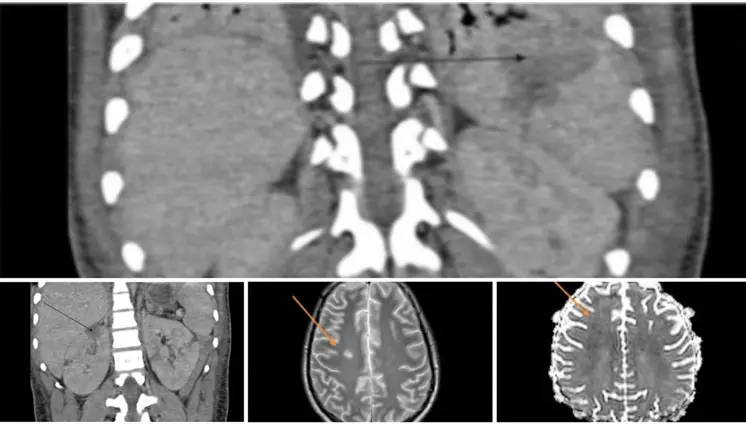

El sistema glinfático, responsable de eliminar desechos cerebrales, al verse alterado, no podría eliminar las proteínas neurotóxicas como la amiloide y tau, las cuales se acumulan en el cerebro en enfermedades neurodegenerativas.